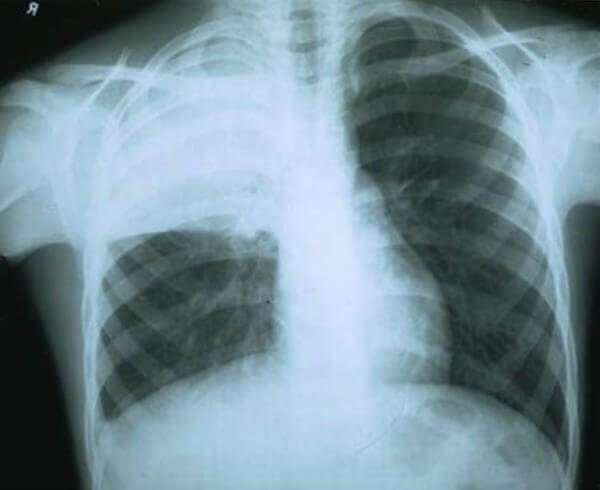

Правосторонняя пневмония на снимке фото

Фото1

Первый признак пневмонии на рентгеновском снимке – появление очагов затемнения с неровными контурами в разных частях легкого, которые могут иметь разный размер, от 3-4-х до 12 мм.

Фото3

Тени различают по внешнему виду (круглые, овальные кольцевидные) и интенсивности окраски – чем темнее пятно, тем сильнее выражен патологический процесс.